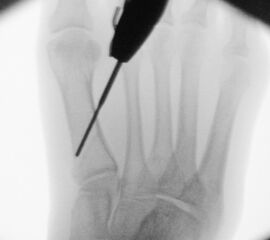

Zusätzlich schränken Wachstumsfugen die Wahl der Osteosynthese ein. Eine die Fuge kreuzende Osteosynthese ist ausschließlich mit Kirschner-Drähten möglich (Abb. 3).

Abb. 3 a-j: Beispiel einer Calcaneusverschiebeosteotomie mit offenen Wachstumsfugen und der entsprechenden Osteosynthese mit Kirschner Drähten. Lokalisation der Osteotomie (a), Lage der Fräse (b-d), Drahtlage mehrere Ansichten (e-h), Heilung der Osteotomie 4 Wochen postoperativ und Entfernung der Drähte (i-j).

Zum Lesen der Bildbeschreibung und zur Vollansicht bitte die Bilder anklicken. Bilder: A. Helmers.

Calcaneus-Osteotomie

Die minimalinvasive Calcaneusverschiebeosteotomie bietet eindeutige Vorteile gegenüber dem offenen Verfahren, sodass wir bei Kindern und Jugendlichen nahezu keine offene Verschiebeosteotomie mehr durchführen. Am Calcaneus liegt die offene Wachstumsfuge dorsal. Bei der Durchführung müssen Schenkel der V-förmigen Osteotomie daher etwas steiler angelegt werden, in einem stumpfen Winkel (siehe Abb. 3 a-j). Für die Osteotomie liegen unsere Patienten auf dem Rücken und der BV wird für die exakte Seitaufnahme eingestellt. Der Fuß lagert auf einem hohen OP-Kissen und die Osteotomie kann bequem mit einem langen Kirschner-Draht und einem sterilen Stift angezeichnet werden (Abb. 15).